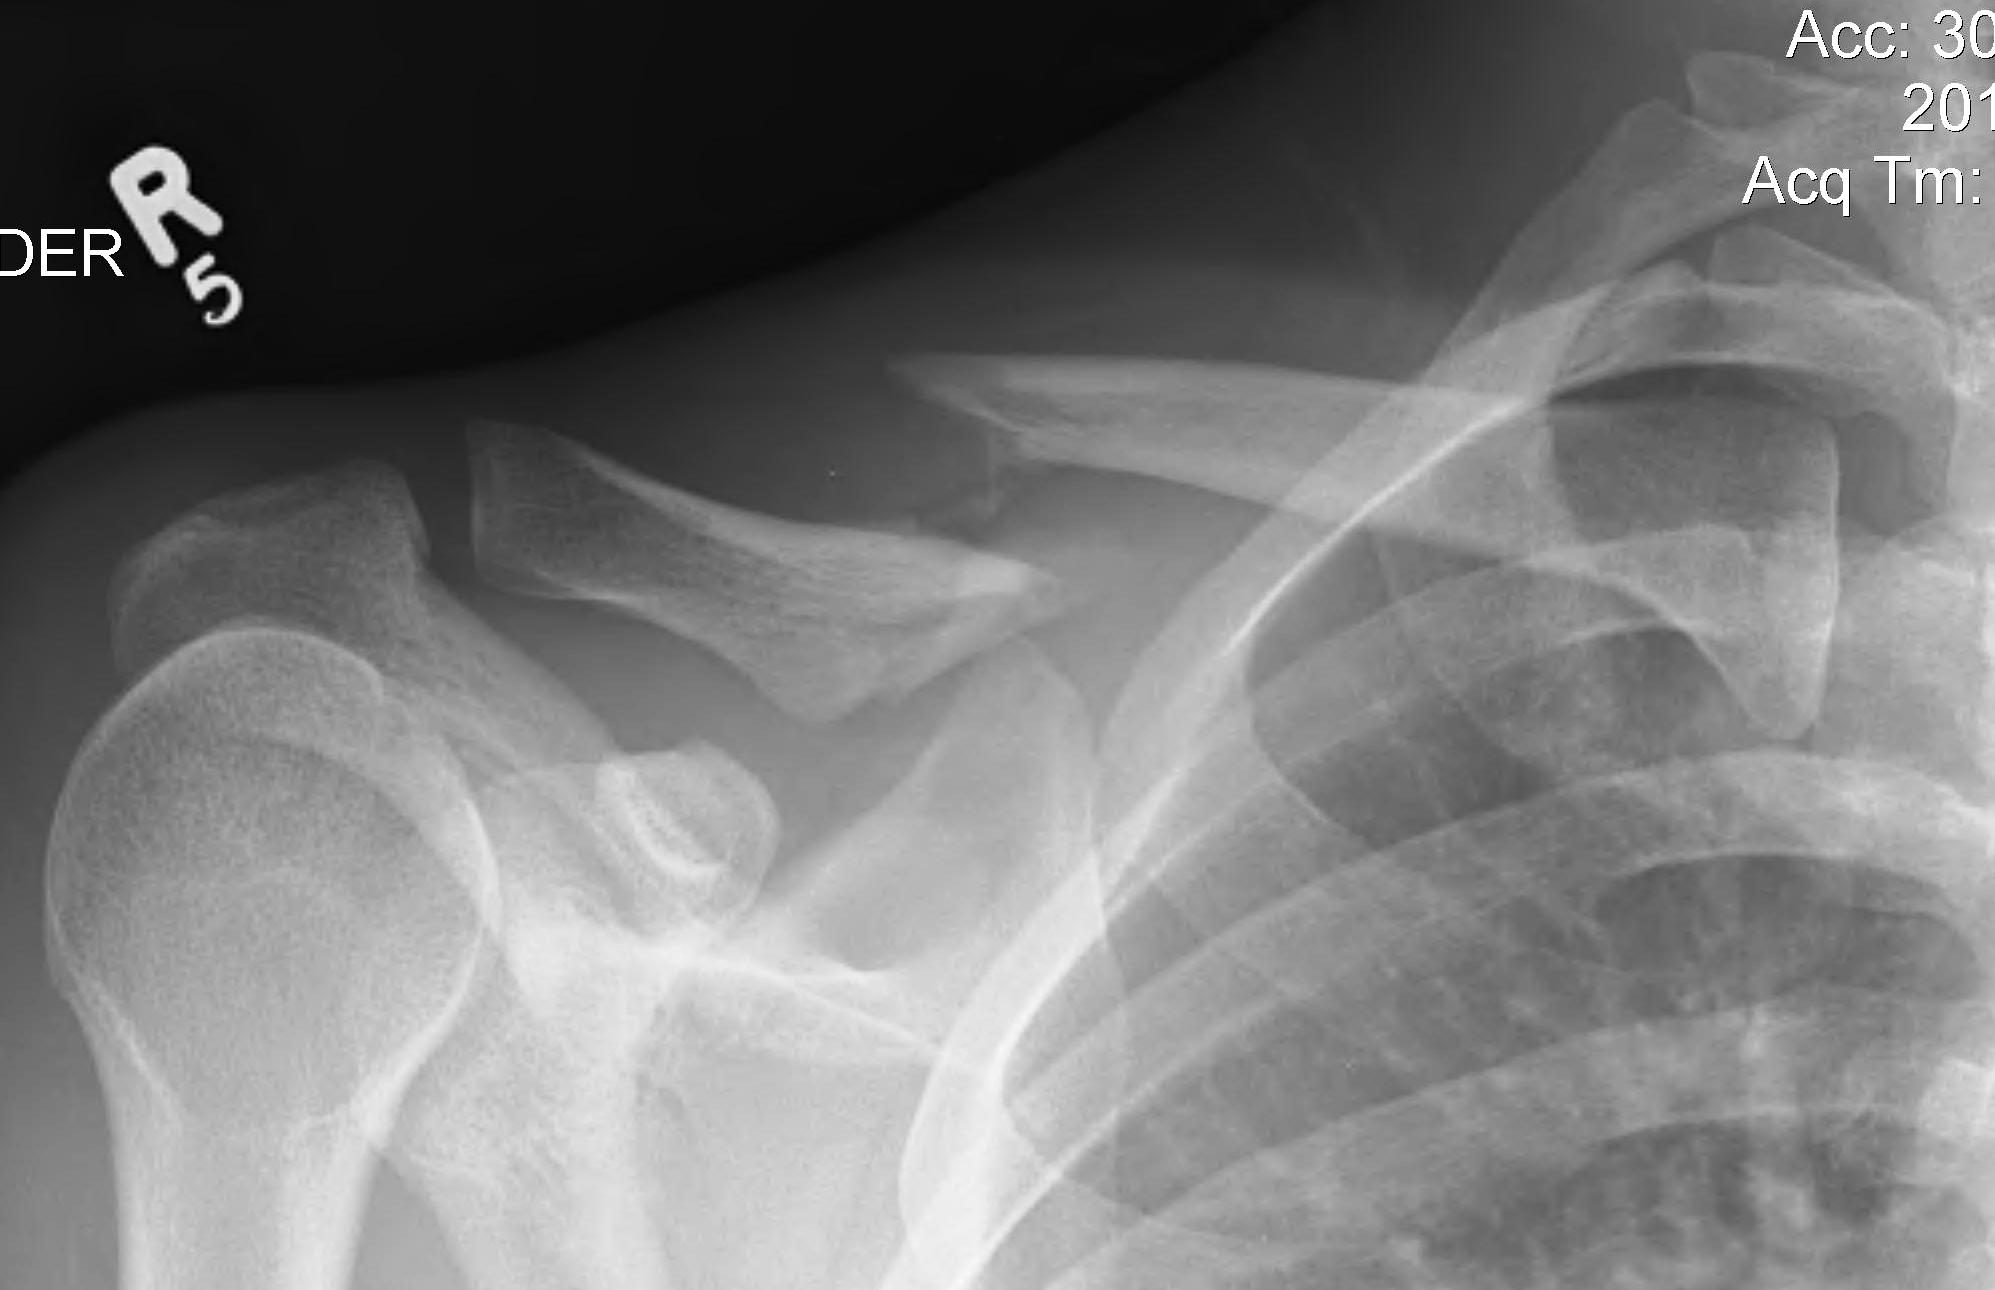

Ache Under Clavicle. If you experience these symptoms, go straight to the emergency room: A ruptured spleen is a medical emergency. This pain can be caused by various factors, ranging from minor injuries to underlying medical conditions. Symptoms of a clavicle fracture is a pain in your upper chest and shoulder area, especially when you’re moving around. How would i treat a fracture? There also can be an obvious deformity in the shoulder, if severe. collarbone pain can be caused by a fracture, arthritis, a bone infection, or another condition related to the position of your clavicle. collarbone pain, also known as clavicle pain, can be a discomforting sensation experienced in the bone that connects the shoulder to the chest. You have two collarbones—one on each side of the front of your chest—that. why your collarbone is sore. Other symptoms include swelling, bruising, tenderness in the shoulder or collarbone area, and dizziness. it may feel like an ache in the spot where the top of the shoulder meets the end of the collarbone.

Other symptoms include swelling, bruising, tenderness in the shoulder or collarbone area, and dizziness. This pain can be caused by various factors, ranging from minor injuries to underlying medical conditions. If you experience these symptoms, go straight to the emergency room: A ruptured spleen is a medical emergency. collarbone pain can be caused by a fracture, arthritis, a bone infection, or another condition related to the position of your clavicle. it may feel like an ache in the spot where the top of the shoulder meets the end of the collarbone. How would i treat a fracture? You have two collarbones—one on each side of the front of your chest—that. Symptoms of a clavicle fracture is a pain in your upper chest and shoulder area, especially when you’re moving around. There also can be an obvious deformity in the shoulder, if severe.

Ache Under Clavicle This pain can be caused by various factors, ranging from minor injuries to underlying medical conditions. collarbone pain, also known as clavicle pain, can be a discomforting sensation experienced in the bone that connects the shoulder to the chest. This pain can be caused by various factors, ranging from minor injuries to underlying medical conditions. Other symptoms include swelling, bruising, tenderness in the shoulder or collarbone area, and dizziness. why your collarbone is sore. If you experience these symptoms, go straight to the emergency room: You have two collarbones—one on each side of the front of your chest—that. There also can be an obvious deformity in the shoulder, if severe. How would i treat a fracture? Symptoms of a clavicle fracture is a pain in your upper chest and shoulder area, especially when you’re moving around. A ruptured spleen is a medical emergency. it may feel like an ache in the spot where the top of the shoulder meets the end of the collarbone. collarbone pain can be caused by a fracture, arthritis, a bone infection, or another condition related to the position of your clavicle.